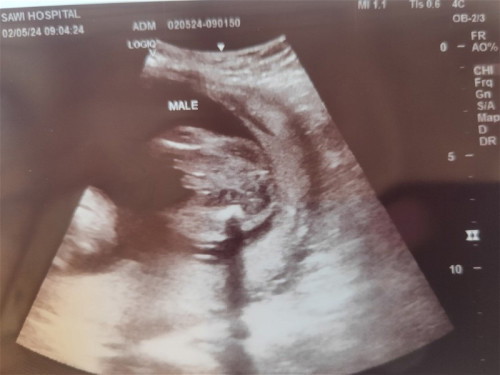

ซาวตอน19วีค คุณหมอบอกว่าน้องผู้ชายค่ะแต่ลูกอันฑะยังไม่สมบูรณ์ แม่ๆว่ายังไงกันบ้างค่ะ